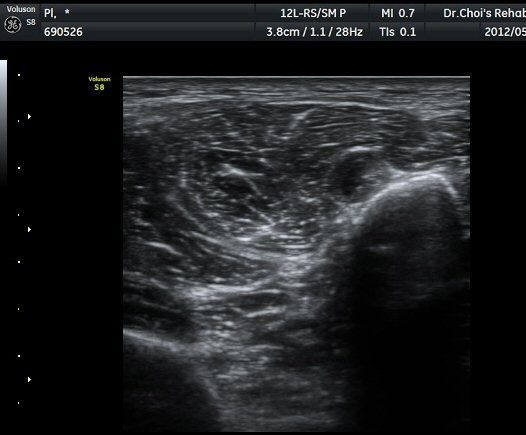

ŽÃËÀÚ¸¦ ¾Æ·¡·Î À̵¿ÇÏ¿© ºñ°ñµÎ ºÎÀ§±îÁö ÃѺñ°ñ½Å°æÀÇ ÁÖÇàÀ» µû¶ó ½Å°æÀ» È®ÀÎÇÏ¿´´Ù(±×¸² 3, 4).